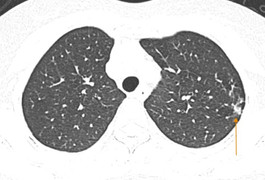

Hà Nội ghi nhận số ca cúm mùa ở trẻ nhỏ tăng mạnh, nhiều bé nhập viện trong tình trạng viêm phổi, co giật, thậm chí suy hô hấp nặng.

Ngoài các triệu chứng sốt, ho, đau họng, trẻ nhiễm cúm A thường sốt cao, da mắt sung huyết, nặng có cảm giác khó thở, viêm phổi, viêm tiểu phế quản.

Những người có hệ miễn dịch yếu, người sẵn bệnh nền, người cao tuổi thường có nguy cơ bị virus tấn công mạnh vào hệ hô hấp, gây ra những biến chứng nguy hiểm.

Suy hô hấp sau khi mắc cúm A, cụ ông nhập viện phải mở nội khí quản, thở máy và đang được điều trị tích cực.